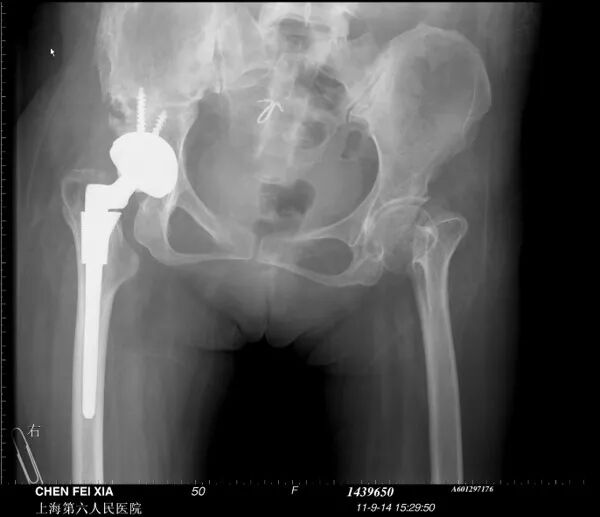

单看股骨侧,大转子顶点和股骨头旋转中心的关系恢复了

但髋臼旋转中心点上移了造成了患肢术后肢体短缩因此如果术中发现髋臼旋转中心点有上移或下移,股骨假体也应相应的吊高或下沉以获得双下肢等长

术后股骨头旋转中心点增高,导致患肢延长